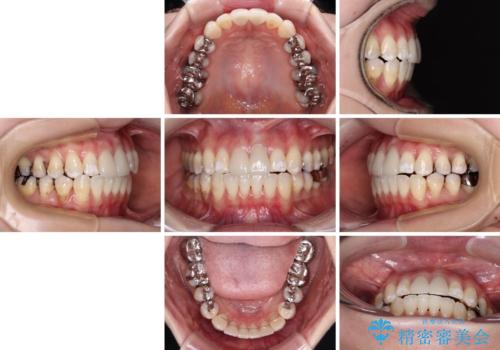

気になる前歯 ワイヤー矯正とセラミック治療

- 30代女性

- 矯正装置

- クリアブラケット

- 前歯のデコボコとセラミッククラウン周りの黒い縁を気にして来院された患者様です。

ワイヤー装置、マウスピース、どちらの装置でも治療は可能でしたが、マウスピース矯正の自己管理の煩わしさを懸念され、ワイヤー装置にて矯正治療を行うこととしました。

前歯の黒い縁は、矯正治療後にオールセラミッククラウンにて改善することとしましたが、いち早く目立たなくしたいとのことで、事前に矯正治療用仮歯に置き換えてから矯正治療を開始しました。

前歯を早々に仮歯に置き換えたことで、矯正治療に意欲的に臨んでくださいました。

口元が前方に突出することもなく、綺麗に仕上げることができました。